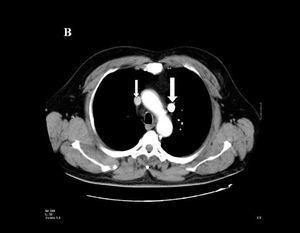

Paciente varón, de 44 años de edad, sometido a implante de marcapasos definitivo debido a un bloqueo aurículo-ventricular de tercer grado, de causa desconocida al no tomar medicación concomitante que pudiera explicar el trastorno de la conducción, ni tener antecedentes clínicos que pudieran justificarlo. Durante el implante los electrodos auricular y ventricular son introducidos a través de la vena subclavia izquierda, y se observa en la escopia que ambos avanzan en dirección caudal por el borde paraesternal izquierdo, confirmándose esta posición en la radiografía posteroanterior de tórax (fig. 1). Los electrodos se encuentran implantados en la aurícula derecha y ventrículo derecho, la amplitud de los sensados y umbrales es correcta. Algunos días más tarde se realiza tomografía axial computarizada torácica (fig. 2), que muestra la vena cava superior (flecha pequeña) y una vena cava superior izquierda (flecha grande), conteniendo ésta última ambos electrodos en su interior.

Figura 2. Tomografía axial computarizada torácica, mostrando la cava superior normal (flecha pequeña) y demostrando la existencia de una vena cava superior izquierda (flecha grande).